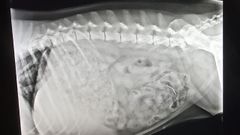

Dueños de perros de Ourense ven con alivio la detención del hombre que ponía cebos con puntas

«Estamos más tranquilos, hasta ahora era estar todo el rato con cien ojos, controlando que el animal no cogiese nada»